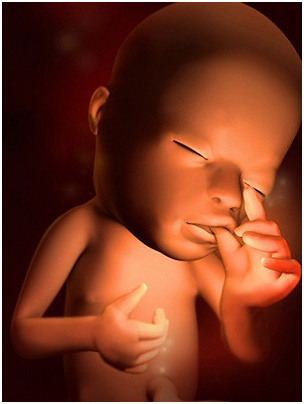

怀孕第9周胎儿图 B超图 三维图 那么,现在恭喜作为准妈妈的你,因为从现在开始,胚胎可...

怀孕第9周胎儿图 B超图 三维图 那么,现在恭喜作为准妈妈的你,因为从现在开始,胚胎可... -